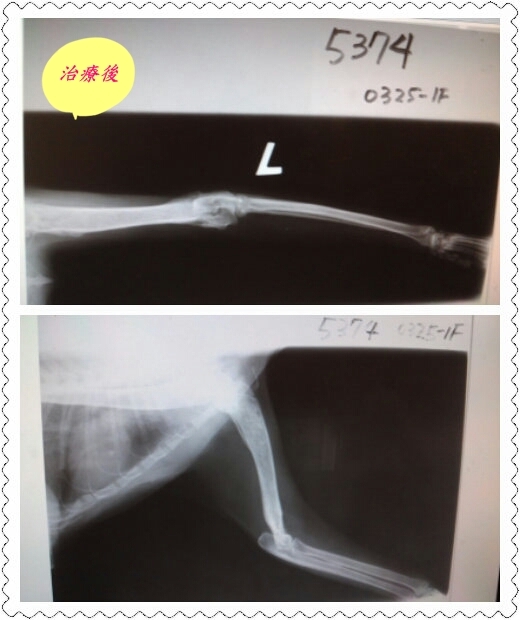

主題: 小港7-11門前蜂窩性組織炎與骨髓炎的貓咪 申請者姓名: 劉雅雲 花色: 申請日期: 2013-05-01 20:58:13 申請者部落格: 申請者臉書網址: 所在縣市/合作醫院: 高雄市/樂生動物醫院 治療費用: 15800元 需求人數: 35人 已結案 (2013-06-27 14:34:12) 報名人員: 飛飛(已付款)、姚怪賢(已付款)、Naima x2(已付款)、chiawei(已付款)、chiawei x2(已付款)、小圓(已付款)、Betty Ou(已付款)、Betty Ou(已付款)、Emily Chou x10(已付款)、兔唒(已付款)、Yvette Lai(已付款)、Yvette Lai(已付款)、Sugar Ring(已付款)、Natasha Chen(已付款)、伶(已付款)、Kiki Liang(已付款)、Gini Hung(已付款)、ERic YU x4(已付款)、波波(已付款)、hero178 x2(已付款)、 候補人員: 動物病情說明: 這是在小港上班附近的7-11, 門口有一隻貓腳受傷了一段時間, 傷口已腫大並滲血水出來, 可能是貓腳傷不舒服或是發情所以會一直叫, 附近居民開始抱怨這隻貓, 這貓咪非常親人, 我用罐頭和外出籠就抓到她, 並趕緊送

到醫院治療腳傷. 可能是因為傷已有一段時間引起骨髓炎, 經過一段時間治療目前貓復原了, 因為非常親人會安置下來幫他找家.

3.X光片 300*4= 1200